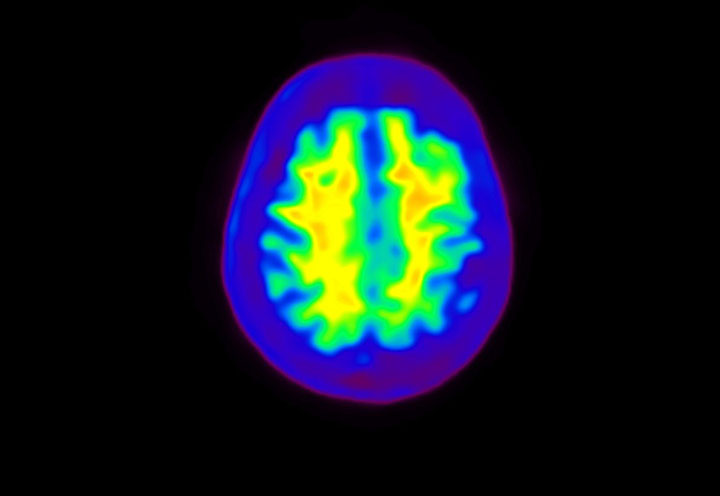

Head / Case4 : Amyloid

Courtesy : Kindai University Hospital

- Imaging protocol

- Injected dose: 3.21 MBq/kg, 18F-Flutemetamol

- Uptake time: 100 minutes

- Scan time: 20 minutes